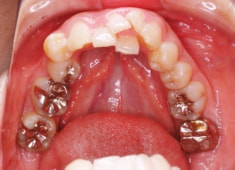

治療前